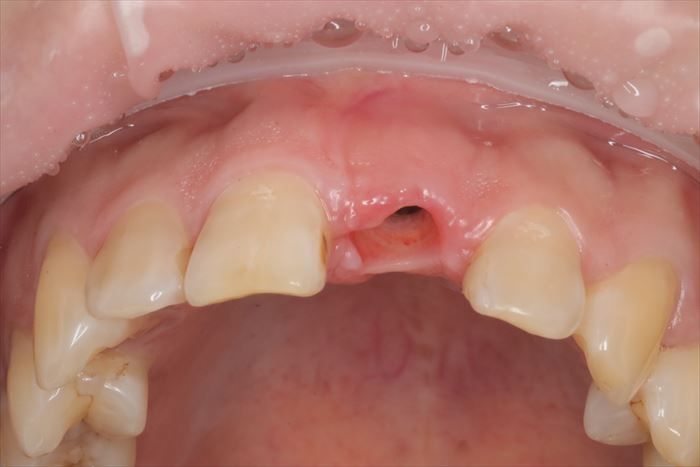

本日は、慣れと咬み合わせの確認のため、プラスチック製の仮歯をセットします。

問題無ければセラミック製のかぶせものをセットして完成です。

初診時の状態です。